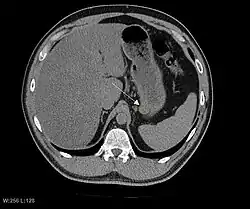

Imaging

The purpose of radiologic imaging is to locate the lesion, evaluate for signs of invasion and detect metastasis. Features of GIST vary depending on tumor size and organ of origin. The diameter can range from a few millimeters to more than 30 cm. Larger tumors usually cause symptoms in contrast to those found incidentally which tend to be smaller and have better prognosis.[4][20] Large tumors tend to exhibit malignant behavior but small GISTs may also demonstrate clinically aggressive behavior.[21]

Preferred imaging modalities in the evaluation of GISTs are CT and MRI,[23]: 20–21 and, in selected situations, endoscopic ultrasound. CT advantages include its ability to demonstrate evidence of nearby organ invasion, ascites, and metastases. The ability of an MRI to produce images in multiple planes is helpful in determining the bowel as the organ of origin (which is difficult when the tumor is very large), facilitating diagnosis.

.jpg)

Since GISTs arise from the bowel layer called muscularis propria (which is deeper to the mucosa and submucosa from a luminal perspective), small GIST imaging usually suggest a submucosal process or a mass within the bowel wall. In barium swallow studies, these GISTs most commonly present with smooth borders forming right or obtuse angles with the nearby bowel wall, as seen with any other intramural mass. The mucosal surface is usually intact except for areas of ulceration, which are generally present in 50% of GISTs. Ulcerations fill with barium causing a bull's eye or target lesion appearance. In contrast-enhanced CT, small GISTs are seen as smooth, sharply defined intramural masses with homogeneous attenuation.

Large GISTs

As the tumor grows it may project outside the bowel (exophytic growth) and/or inside the bowel (intraluminal growth), but they most commonly grow exophytically such that the bulk of the tumor projects into the abdominal cavity. If the tumor outstrips its blood supply, it can necrose internally, creating a central fluid-filled cavity with bleeding and cavitations that can eventually ulcerate and communicate into the lumen of the bowel. In that case, barium swallow may show an air, air-fluid levels or oral contrast media accumulation within these areas.[21][25] Mucosal ulcerations may also be present. In contrast-enhanced CT images, large GISTs appear as heterogeneous masses due to areas of living tumor cells surrounding bleeding, necrosis or cysts, which is radiographically seen as a peripheral enhancement pattern with a low attenuation center.[20] In MRI studies, the degree of necrosis and bleeding affects the signal intensity pattern. Areas of bleeding within the tumor will vary its signal intensity depending on how long ago the bleeding occurred. The solid portions of the tumor are typically low signal intensity on T1-weighted images, are high signal intensity on T2-weighted images and enhanced after administration of gadolinium. Signal-intensity voids are present if there is gas within areas of necrotic tumor.[22][26][27]

Features of malignancy

Malignancy is characterized by local invasion and metastases, usually to the liver, omentum and peritoneum. However, cases of metastases to bone, pleura, lungs and retroperitoneum have been seen. In distinction to gastric adenocarcinoma or gastric/small bowel lymphoma, malignant lymphadenopathy (swollen lymph nodes) is uncommon (<10%) and thus imaging usually shows absence of lymph node enlargement.[20] If metastases are not present, other radiologic features suggesting malignancy include: size (>5 cm), heterogeneous enhancement after contrast administration, and ulcerations.[4][20][28] Also, overtly malignant behavior (in distinction to malignant potential of lesser degree) is less commonly seen in gastric tumors, with a ratio of behaviorally benign to overtly malignant of 3-5:1.[4] Even if radiographic malignant features are present, these findings may also represent other tumors and definitive diagnosis must be made immunochemically.